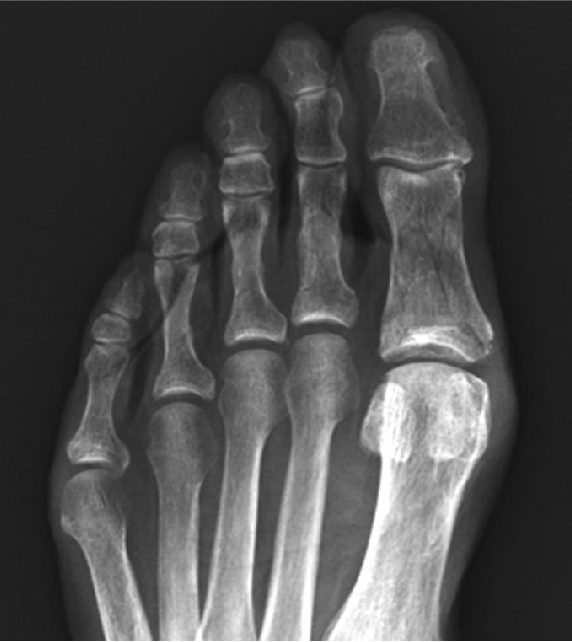

有護趾片保護

從上圖可見,有護趾片保護的情況下,重物不會直接撞擊到腳趾,因此骨頭仍是完好無損。

無護趾片保護

無護趾片保護的腳趾,直接被重物撞擊,可發現五隻腳趾的骨頭均被壓傷變形,大拇趾甚至已有粉碎性骨折。